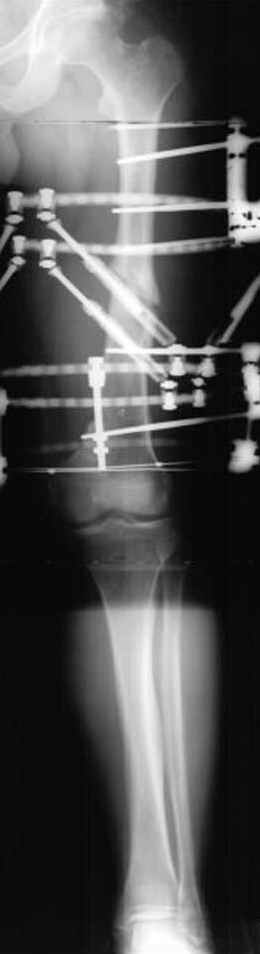

Несколько снимков из моей коллекции, чтобы разьяснить, почему мы до сих пор делаем различные варианты остеотомии.

На рисунке N1 предоперационный план лечения ложного сустава шейки бедра- линия ложного сустава, угол и направление введения импланта, клиновидная остеотомия в градусах и миллиметрах, второй снимок после коррекции, расчет, на сколько удлиняется конечность и размеры импланта;

N3 рисунок окончательный снимок, после операции моя рентгенограмма должен выглядеть примерно как эта картина. На N4 снимке клин перед удалением; N5 послеоперации 3 нед.; N6 окончательная рентгенограмма.

Отправитель: Djoldas Kuldjanov 23 Ноябрь 2004, 18:21

пластическая модель; и коррекция бедра аппаратом Илизарова.